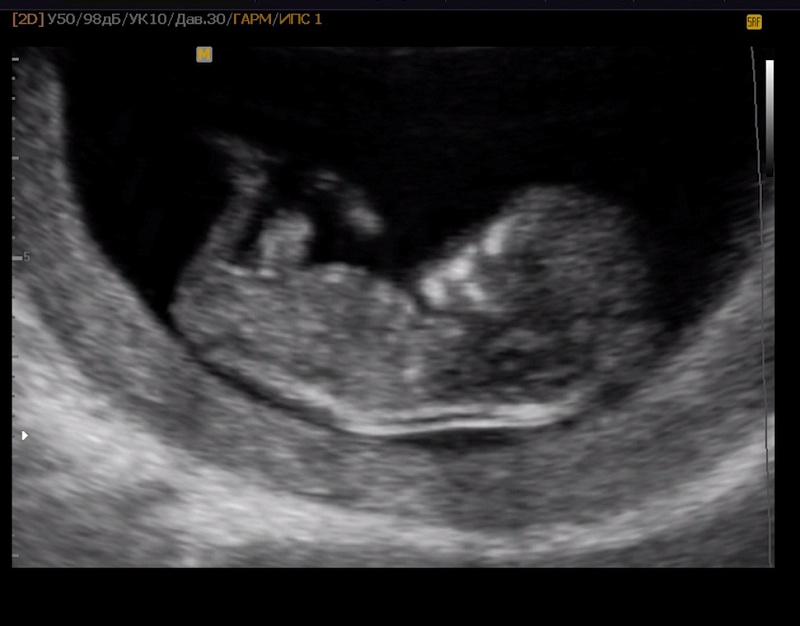

2D УЗИ - это стандартный режим, где получается черно-белое изображение в плоскости. Он используется для измерения размеров плода, оценки строения внутренних органов и работы сердца в реальном времени.

36e5b49ed94d760f4409549a8913d252.jpg